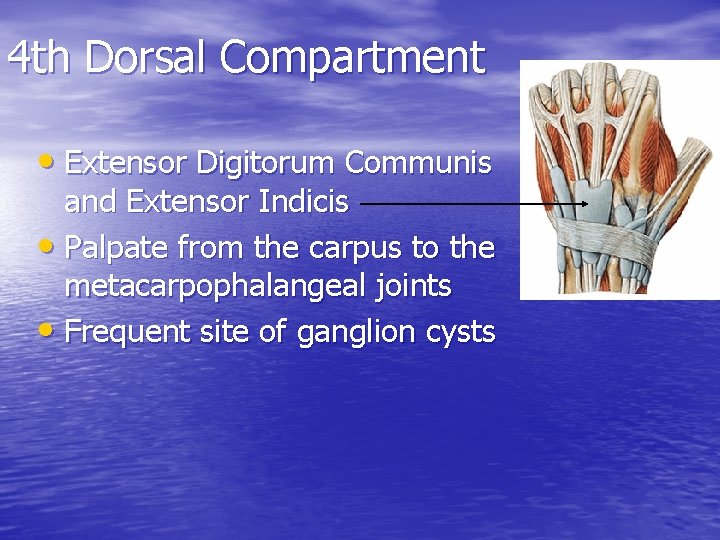

4 th Dorsal Compartment • Extensor Digitorum Communis and Extensor Indicis • Palpate from the carpus to the metacarpophalangeal joints • Frequent site of ganglion cysts